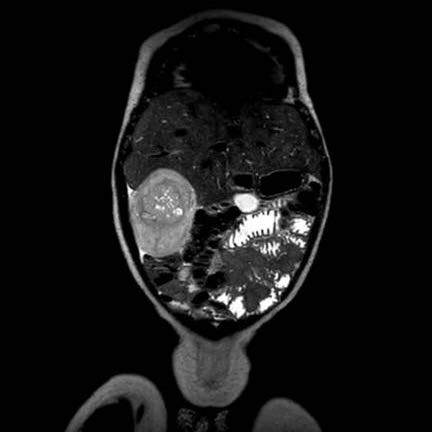

Ca lâm sàng 1

Hình ảnh chuỗi xung T2W mặt phẳng coronal cho thấy một khối u không đồng nhất ở thận trái với các thành phần nang nhỏ.

Khối u ngấm thuốc kém hơn so với phần nhu mô thận bình thường còn lại ở ngoại vi.

Các thành phần đặc của khối u cho thấy hạn chế khuếch tán rõ rệt (mũi tên).

Đây là u Wilms ở bé trai năm tuổi. Hóa trị tiền phẫu được thực hiện theo phác đồ Umbrella của SIOP-RTSG, sau đó tiến hành cắt thận.